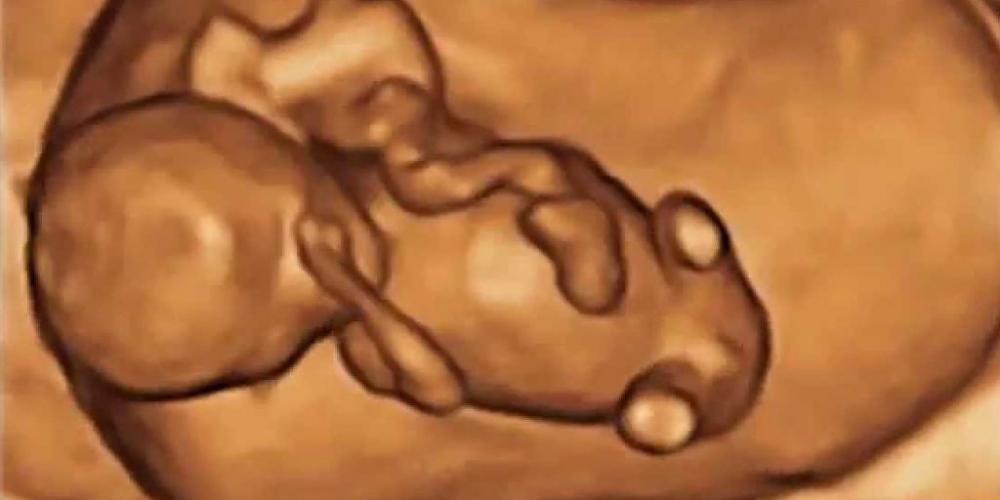

LOS EMBRIONES SON PERSONAS Y MERECEN SER PROTEGIDOS, NO DESCARTADOS

Ante el caso que se conoció en Agosto de 2024 sobre un fallo de la Corte Suprema de Justicia que analizó el pedido de una pareja para descartar a sus hijos en estado embrionario y criopreservados,...

UN NIÑO POR HORA MUERE ABORTADO EN LA CIUDAD DE BUENOS AIRES

La ciudad capital de la Argentina realizó 4.314 abortos durante los 181 días del primer semestre del 2024. El ministerio de Salud de la Ciudad de Buenos Aires -que encabeza Fernán González...